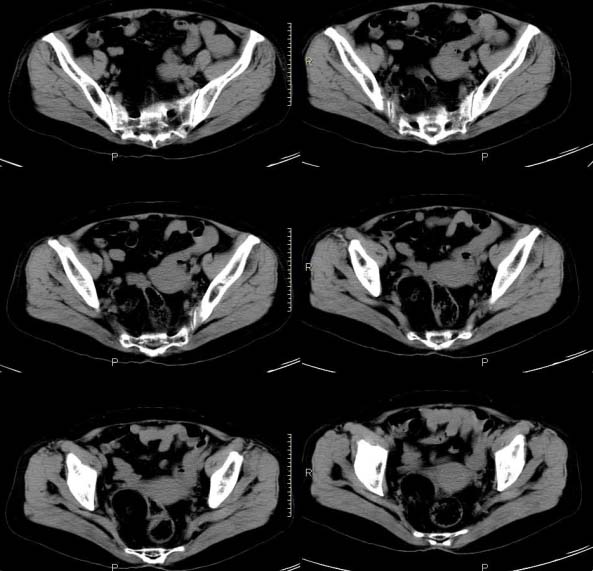

女,63岁,绝经15年,从阴道内有液体流出约1月余,且带有血,患者一般情况很差,在家属搀扶下行走。请大家看看是子宫病变还是宫颈病变?

考虑子宫内膜癌可能性大。建议查hcg等,诊断性刮宫。

子宫颈体积增大,宫颈壁不均匀性增厚,且不均匀性强化。考虑为宫颈ca。

子宫颈内见低密度影,外形不规则,不均匀强化,考虑占位,子宫颈癌可能性大。